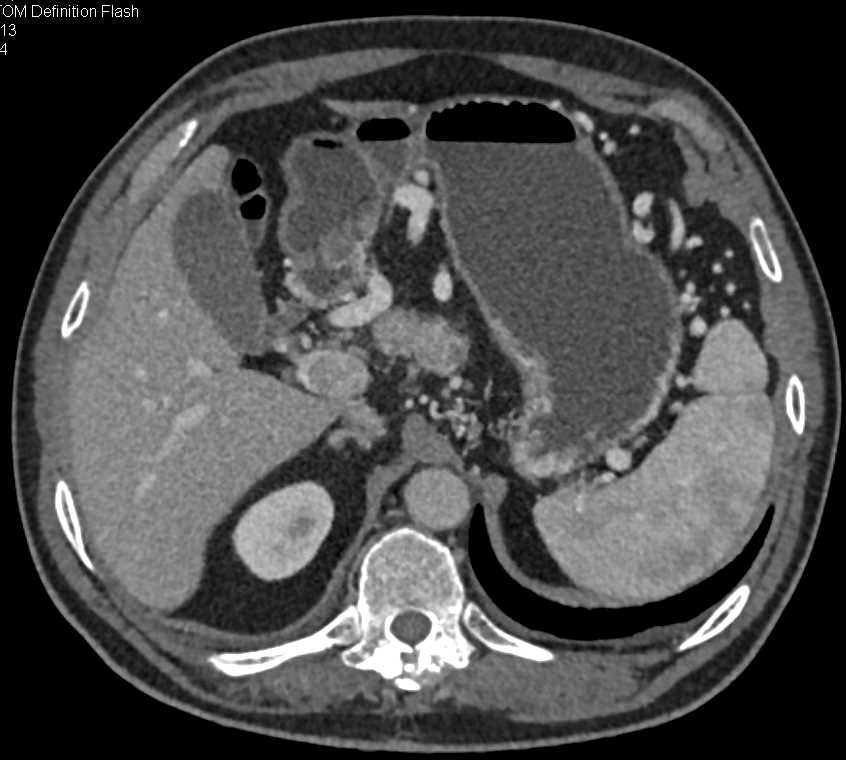

Pancreatic Cancer Causes Gastric Outlet Obstruction